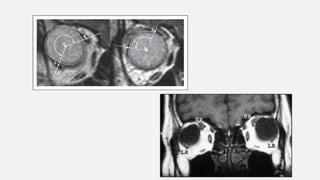

High myopic esotropia :

Key to diagnosis – MRI

- Shows distorted muscle paths

- Displacement of SR muscle nasally – mechanical adduction and limitation

of abduction

- Displacement of LR inferiorly – mechanical depression with limitation of

elevation

- Orbital connective tissue degeneration and associated abnormalities are seen